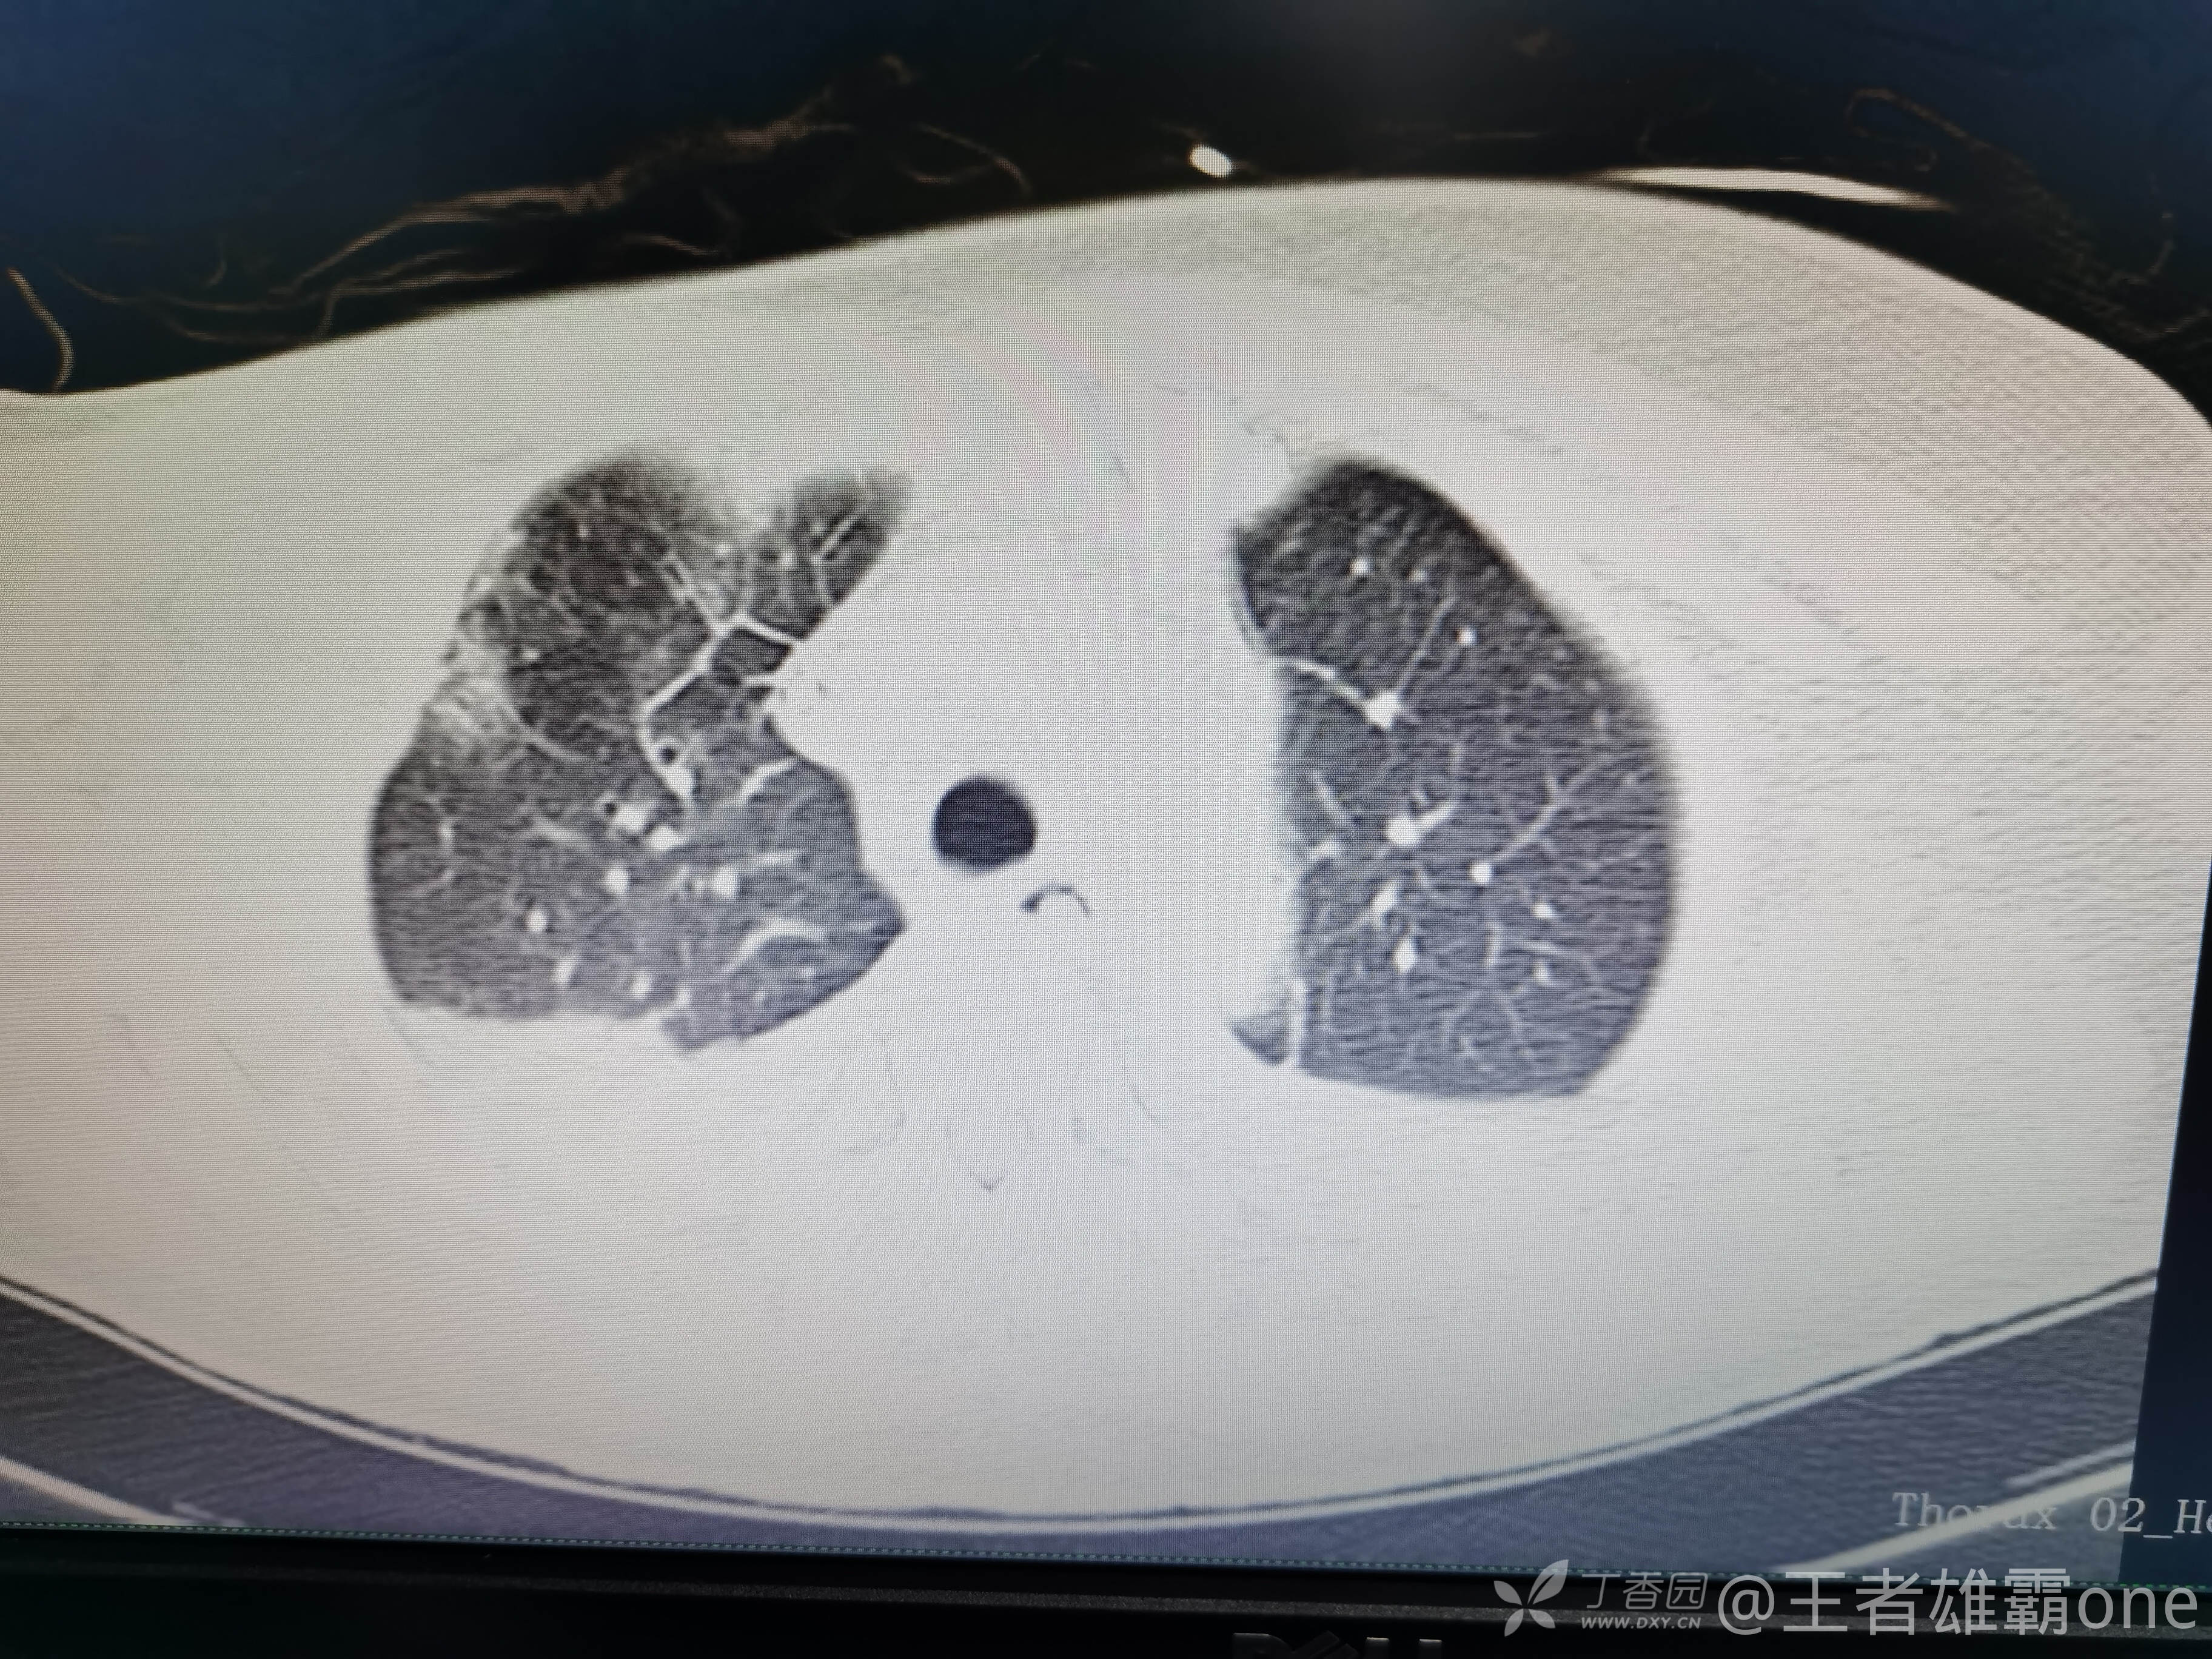

西门开心 推荐63岁女性,因车祸致短暂神志不清、多处疼痛4h入院。简单病史:伤后送至医院急诊就诊。完善头胸腹CT等检查,完善新冠核酸、血常规等化验。血常规提示血红蛋白62g/L。头颅CT提示未见明显外伤性改变。胸腹部CT视频见下:

5.肺挫伤

6.双侧多发肋骨骨折

12.双侧胸腔少量积液